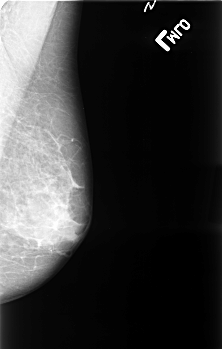

B_3389_1.RIGHT_MLO

ics_version 1.0

filename B-3389-1

DATE_OF_STUDY 17 2 1993

PATIENT_AGE 68

FILM_TYPE REGULAR

DENSITY 3

DATE_DIGITIZED 27 10 1998

DIGITIZER LUMISYS LASER

LEFT_MLO LINES 4528 PIXELS_PER_LINE 2880 BITS_PER_PIXEL 12 RESOLUTION 50 NON_OVERLAY